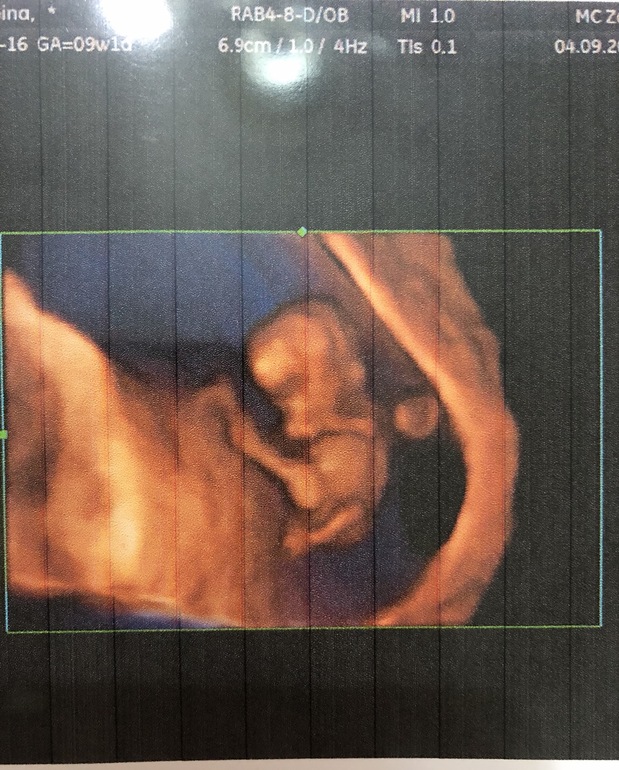

Когда моя малышка была 32 мм (по М 9+1), по ктр ставили 10+1, она уже была сформированным человечком. Так что советую (как и многие тут) переделать узи у хорошего узиста. Это в 9+1 недель.